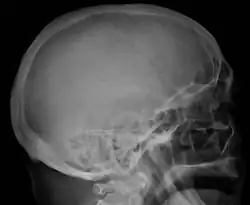

Bone pain affects almost 70% of people with multiple myeloma and is one of the most common symptoms.[2]: 653 [23] Myeloma bone pain usually involves the spine and ribs and worsens with activity. Persistent, localized pain may indicate a pathological bone fracture. Involvement of the vertebrae may lead to spinal cord compression or kyphosis. Myeloma bone disease is due to the overexpression of receptor activator for nuclear factor κ B ligand (RANKL) by bone marrow stroma. RANKL activates osteoclasts, which resorb bone. The resultant bone lesions are lytic (cause breakdown) in nature. They are best seen in plain radiographs, which may show "punched-out" resorptive lesions (including the "raindrop" appearance of the skull on radiography). The breakdown of bone also leads to the release of calcium ions into the blood, leading to hypercalcemia and its associated symptoms.[24]

The diagnostic examination of a person with suspected multiple myeloma typically includes a skeletal survey. This is a series of X-rays of the skull, axial skeleton, and proximal long bones. Myeloma activity sometimes appears as "lytic lesions" (with local disappearance of normal bone due to resorption) or as "punched-out lesions" on the skull X-ray ("raindrop skull"). Lesions may also be sclerotic, which is seen as radiodense.[76] Overall, the radiodensity of myeloma is between −30 and 120 Hounsfield units (HU).[77] Magnetic resonance imaging is more sensitive than simple X-rays in the detection of lytic lesions. An MRI may supersede a skeletal survey, especially when vertebral disease is suspected. Occasionally, a CT scan is performed to measure the size of soft-tissue plasmacytomas. Nuclear Medicine Bone scans are typically not of any additional value in the workup of people with myeloma (no new bone formation; lytic lesions not well visualized on nuclear bone scan).